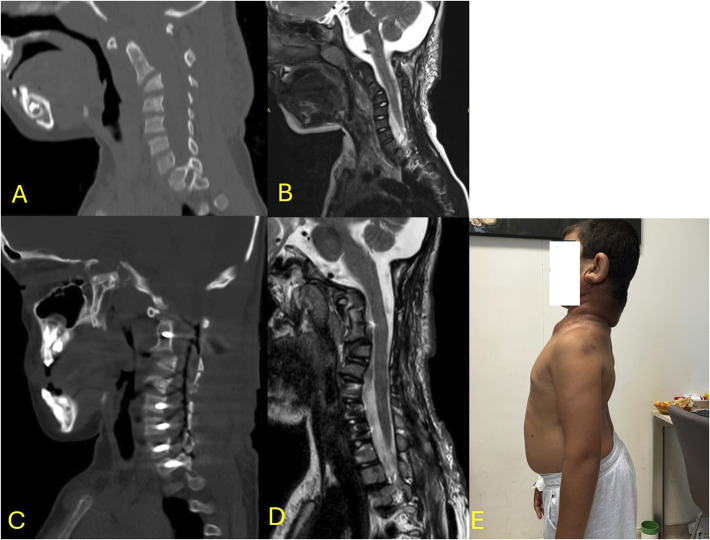

Abstract Image